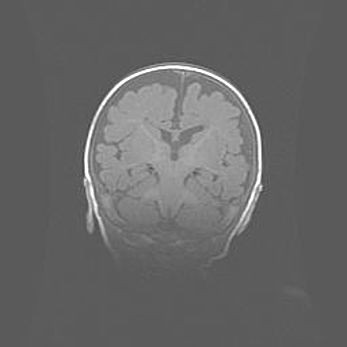

Открытая гидроцефалия.

Возраст: 6 месяцев 15 дней

Вес: 6200 г

Пол: женский

Окружность головы: 41 см

Срок гестации: 38 недель

Гидроцефалия головного мозга у новорожденных – это скопление избыточного количества цереброспинальной жидкости в головном мозге. Ее избыточное скопление в мозге приводит к патологическому расширению желудочков мозга (четырех полостей, расположенных в глубине белого вещества мозга, заполненных цереброспинальной жидкостью и связанных узкими проходами).

Открытый тип гидроцефалии (сообщающаяся) наблюдается тогда, когда нарушен механизм всасывания ликвора в системный кровоток. При этом типе причиной заболевания чаще всего является перенесенные ранее инфекции (например: менингит),  либо же наличие крови в субарахноидальном пространстве.